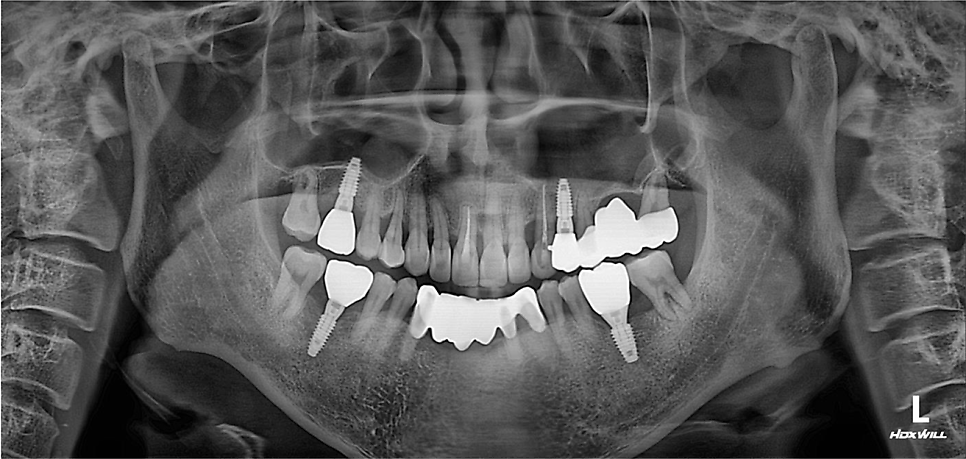

빨간색 : 보철 후 앞니가 벌어짐

노란색: 치조골이 녹아서 잇몸상태가 좋지 않음

파란색: 발치 후 방치하여 어금니가 쓰러짐

위 설명처럼 여러가지 문제가 보입니다.

양쪽 상악동 뼈가 종잇장 정도로만 남아있네요.

임플란트 4개로 마무리 되었습니다.

쓰러진 치아들도 제자리오 잘 세워졌습니다.